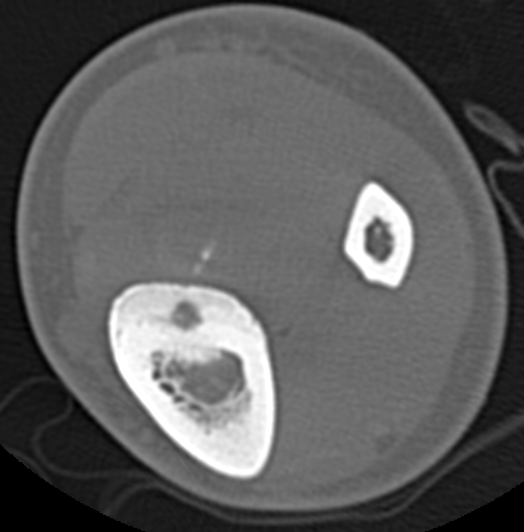

CT

Best investigation

- lucent nidus surrounded by dense bone

Osteoid osteoma tibia

Osteoid osteoma femur